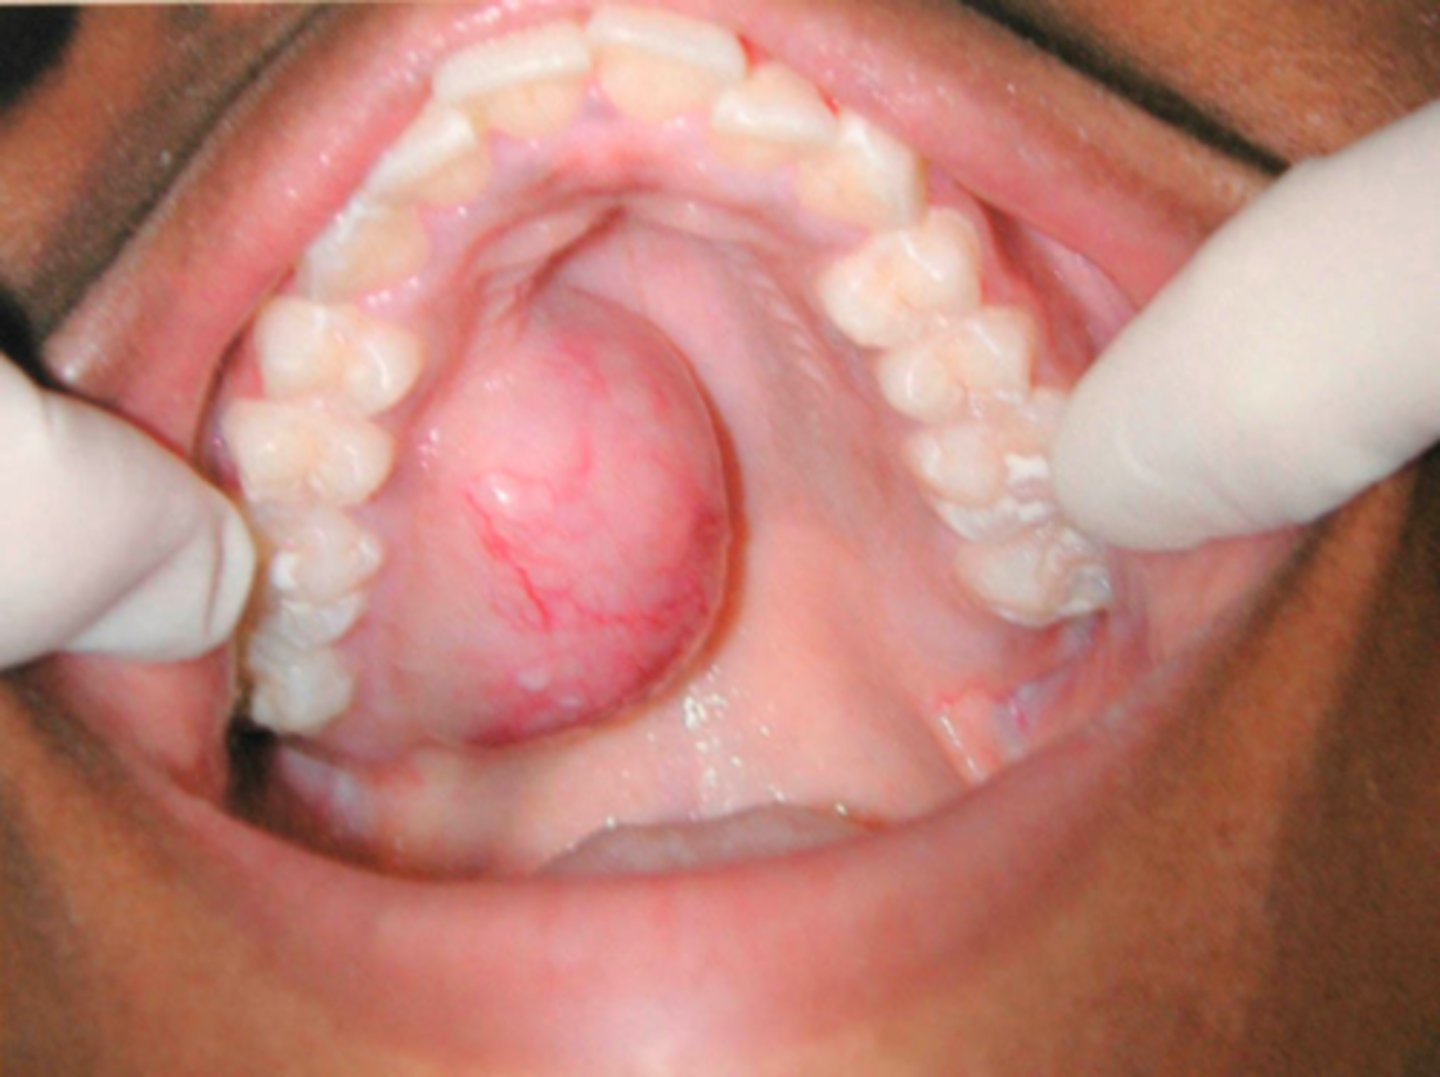

Ranula

A mucocele on floor of mouth is called a ______

sublingual gland

A Ranula is usually associated with what gland?

patient presents with a dome-shaped fluctuant vesicle that looks bluish in color on the floor of the mouth. What is the diagnosis?

floor of mouth

what is the most common location for a Ranula to present?

ID the pathology:

- Ranula

- Salivary duct cyst

- Dermoid/Epidermoid cyst

Patient presents with a large nodule on the floor of the mouth lateral to the midline. What is in your differential diagnosis (3)?

Excisional biopsy with gland

What is the treatment for a ranula?